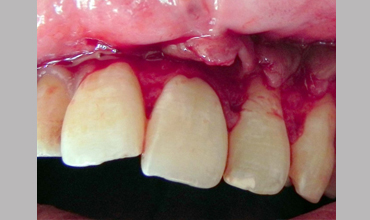

Surgical Management Of Large Periapical Cyst